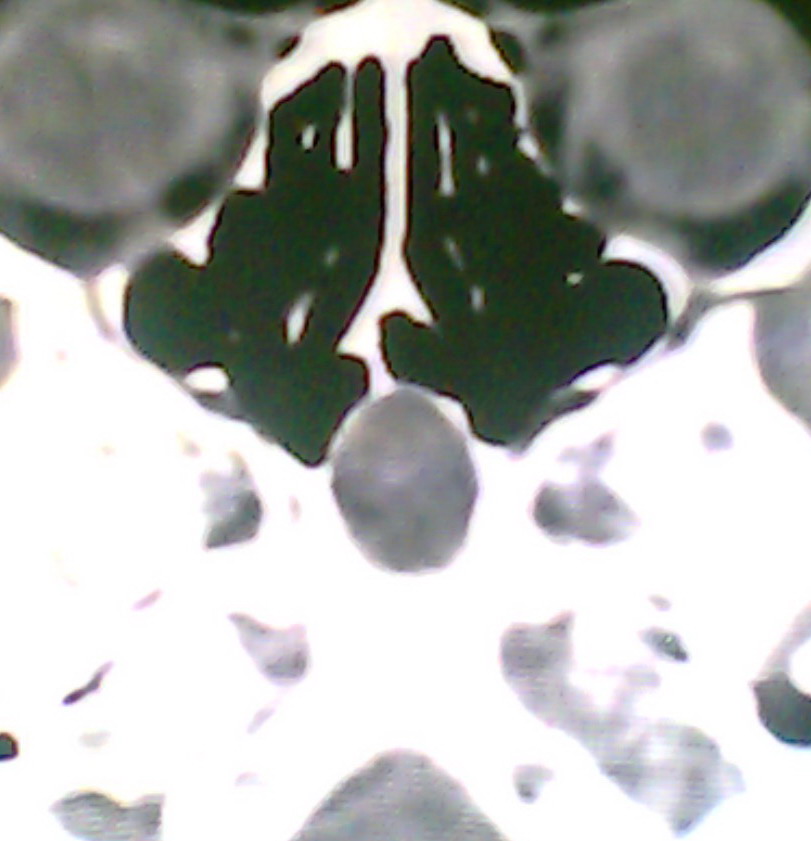

女、18岁,身高1.5左右,鼻塞、流涕数月,两侧瞳孔明显增大,曾与几年前去北京看眼,未发现病变。

考虑起源与蝶窦的粘液囊肿。

考虑脑膜脑脊液鼻内膨出

考虑起源于蝶窦的粘液囊肿突入鼻咽部。

\"几年前去北京看眼\"不知这句话有何玄机,支持考虑脑膜脑脊液鼻内膨出,膨出口在蝶鞍处

建议冠状面扫描,支持:脑膜鼻内膨出; 蝶窦粘液囊肿突入鼻腔可能性小。

在上级医院冠状位ct扫描后,诊断为:脑膜膨出,已住院准备手术。等待术后结果。